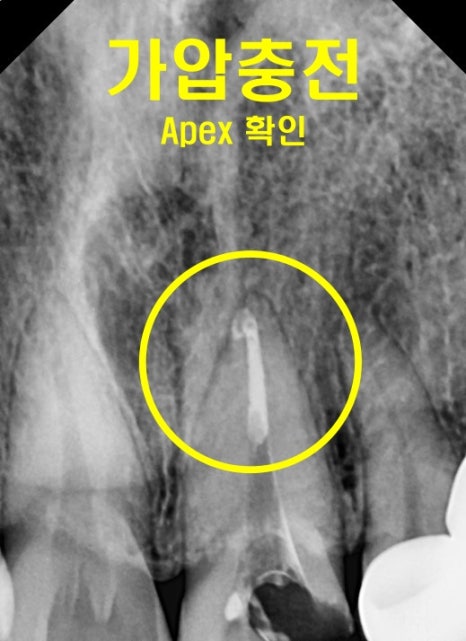

그 뒤에는 속에서부터 청결한 충전재가

잘 밀폐되어 채워지도록

가압충전을 해 주면서 넣어줍니다.

(※ 압력을 줘서 넣어주는 것을 말합니다)

그렇게 치아 뿌리부터 잘 채워줬다면,